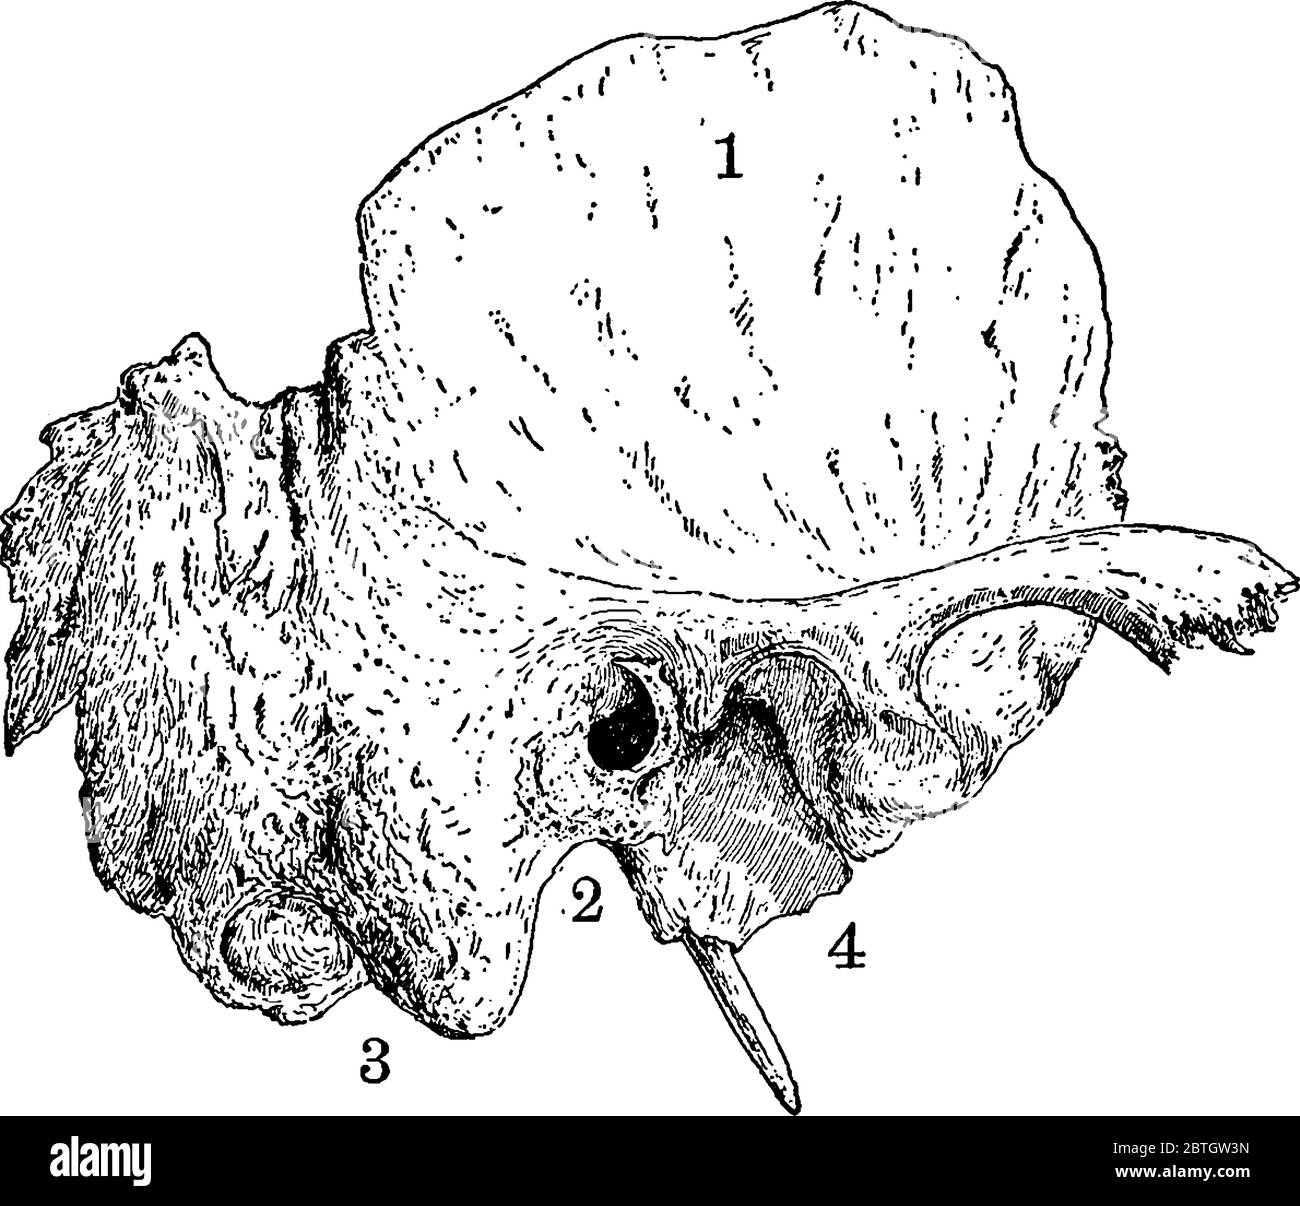

The temporal Bone of the human skull, situated at the sides and base of the skull, with its parts labelled, vintage line drawing or engraving illustra Stock Vectorhttps://www.alamy.com/image-license-details/?v=1https://www.alamy.com/the-temporal-bone-of-the-human-skull-situated-at-the-sides-and-base-of-the-skull-with-its-parts-labelled-vintage-line-drawing-or-engraving-illustra-image359330041.html

The temporal Bone of the human skull, situated at the sides and base of the skull, with its parts labelled, vintage line drawing or engraving illustra Stock Vectorhttps://www.alamy.com/image-license-details/?v=1https://www.alamy.com/the-temporal-bone-of-the-human-skull-situated-at-the-sides-and-base-of-the-skull-with-its-parts-labelled-vintage-line-drawing-or-engraving-illustra-image359330041.htmlRF2BTGW3N–The temporal Bone of the human skull, situated at the sides and base of the skull, with its parts labelled, vintage line drawing or engraving illustra